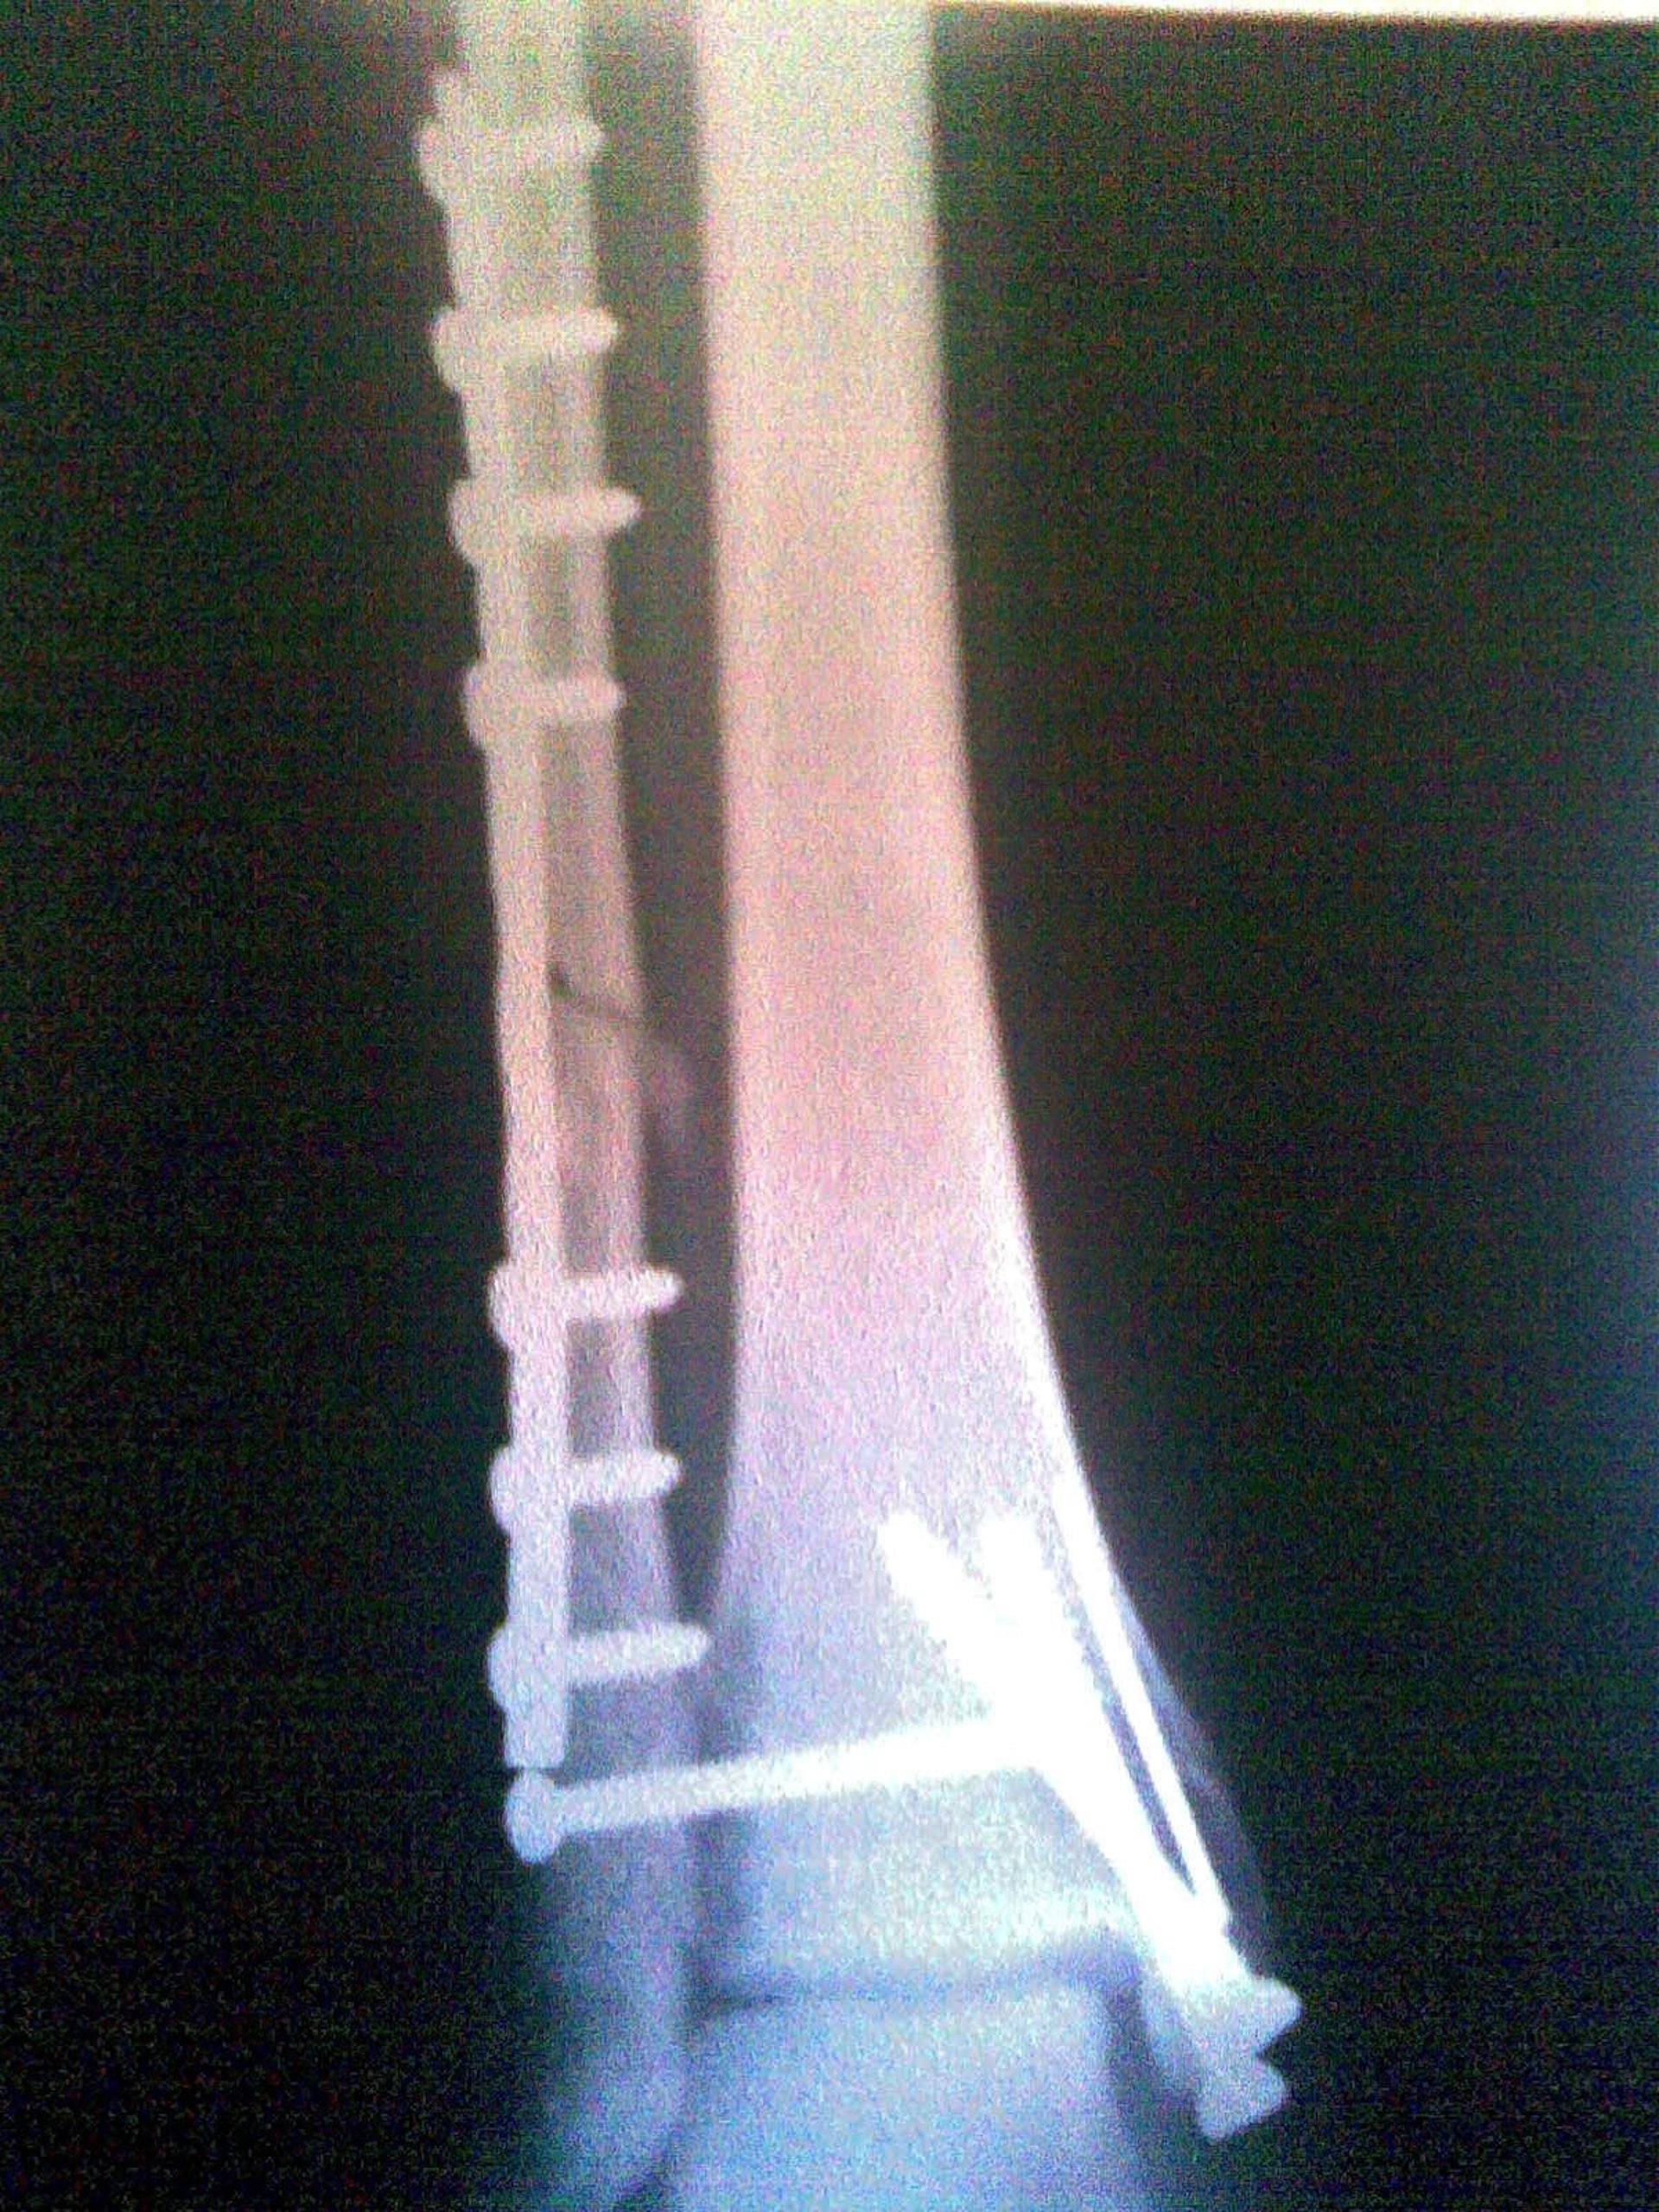

Radiografia, Hueso

Las fracturas óseas tendrán tratamientos personalizados a partir del estudio de una radiografía, con la que se podrá determinar cómo se va a curar el hueso y qué va a necesitar el paciente. Estas son las primeras conclusiones del proyecto europeo CAD-BONE, liderado por un equipo del Instituto de Investigación en Ingeniería de Aragón (I3A) de la Universidad de Zaragoza (UZ).